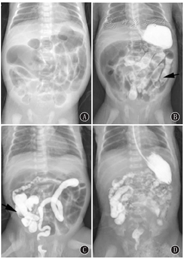

45例患儿腹部CT、胸部CT或胸片均未发现囊性病变。均为汉族。基本情况见表1。45例中24例行末端回肠造瘘术,保守治疗21例。术中所见外观均表现为全结肠型HD样改变,移行段位于距回盲部20~30 cm的末端回肠,移行段近端肠管扩张,扩张肠管直径可达3~4 cm,肠腔内充满黑绿色胎便;移行段远端回肠、结肠管径细小,直径0.5~0.8 cm,腔内充满节段柱状的灰白色成形便块或墨绿色的黏稠胎便,肠壁僵硬似无神经节细胞症状改变(图1)。手术病例患儿回肠的狭窄段、移行段以及扩张段肠管术后病检均可见神经节细胞。住院时间为(21.19±5.13) d,并发症患儿均为手术病例,包括伤口感染(2例)、造瘘肠管脱垂(2例)、术后反复的水电解质紊乱(21例)、营养不良(21例)。肠造瘘病例远端造瘘肠管钡剂排空良好,术中冷冻切片均可见神经节细胞。关瘘术后电话或门诊随访5~9年,患儿并无肠神经节细胞分布异常的临床表现。24例患儿关瘘前均行直肠肛门测压,其中21例结果正常,其余3例结果异常患儿关瘘前的直肠病检提示可见神经节细胞,排除先天性巨结肠,术后1~3个月随访复查,生长发育良好,复查直肠肛门测压结果转为正常。

21例行保守治疗(图2),其住院时间(12.29±3.85) d,直肠肛门测压21例中18例结果正常,3例阳性病例中2例患儿在1月龄及2月龄复查时转为正常,第3例患儿随访中有反复便秘,2岁时在外院行结肠次全切,术后病理检查考虑为肠神经节细胞发育不良,术后痊愈。其余17患儿均能正常进食,无与肠道梗阻相关的并发症,造瘘组和保守治疗组在孕周、出生体质量上差异无统计学意义(P>0.05),但在住院时间上差异有统计学意义(P<0.05)(表1)。